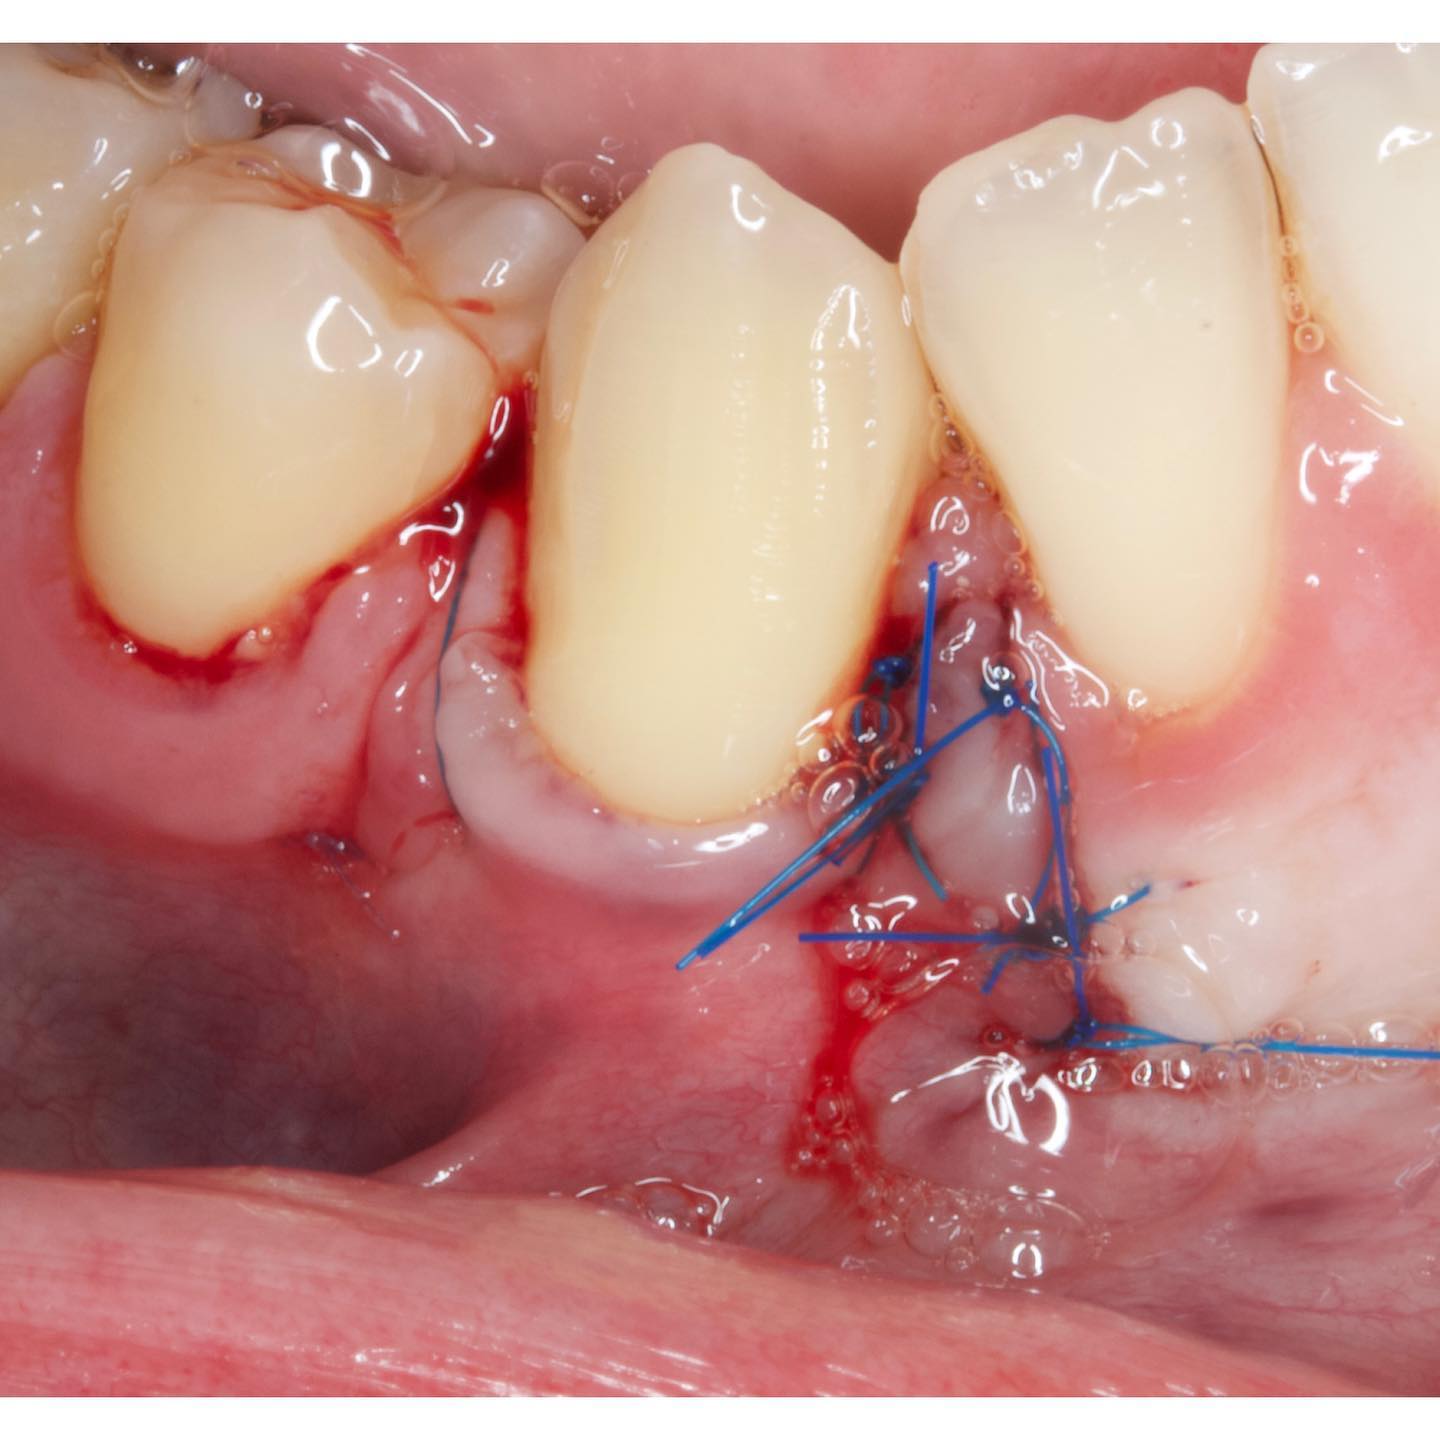

Podrás asistir a la planificación de casos y cirugía de injerto de tejido conectivo. Factores determinantes y elección de la técnica adecuada. Sumérgete en un protocolo predecible y técnicamente correcto para obtener resultados óptimos.

Una estancia clínica pensada para quienes quieran iniciarse o dar un paso más en el campo de la cirugía mucogingival. Durante esta experiencia tendrás la oportunidad de aprender en directo cómo se planifica y se lleva a cabo una cirugía mucogingival mediante técnica de Túnel.

La sesión

Formación teórico-práctica completa sobre las técnicas más avanzadas en cirugía mucogingival. Durante dos días intensivos, los participantes aprenderán desde la evidencia científica y la anatomía de las zonas donantes hasta la ejecución de injertos, cubrimiento radicular y aumento de

Dos cirugías mucogingivales en directo.

Una estancia clínica pensada para quienes quieran iniciarse o dar un paso más en el campo de la cirugía mucogingival. Durante esta experiencia tendrás la oportunidad de aprender en directo cómo se planifica y se lleva a cabo una cirugía mucogingival